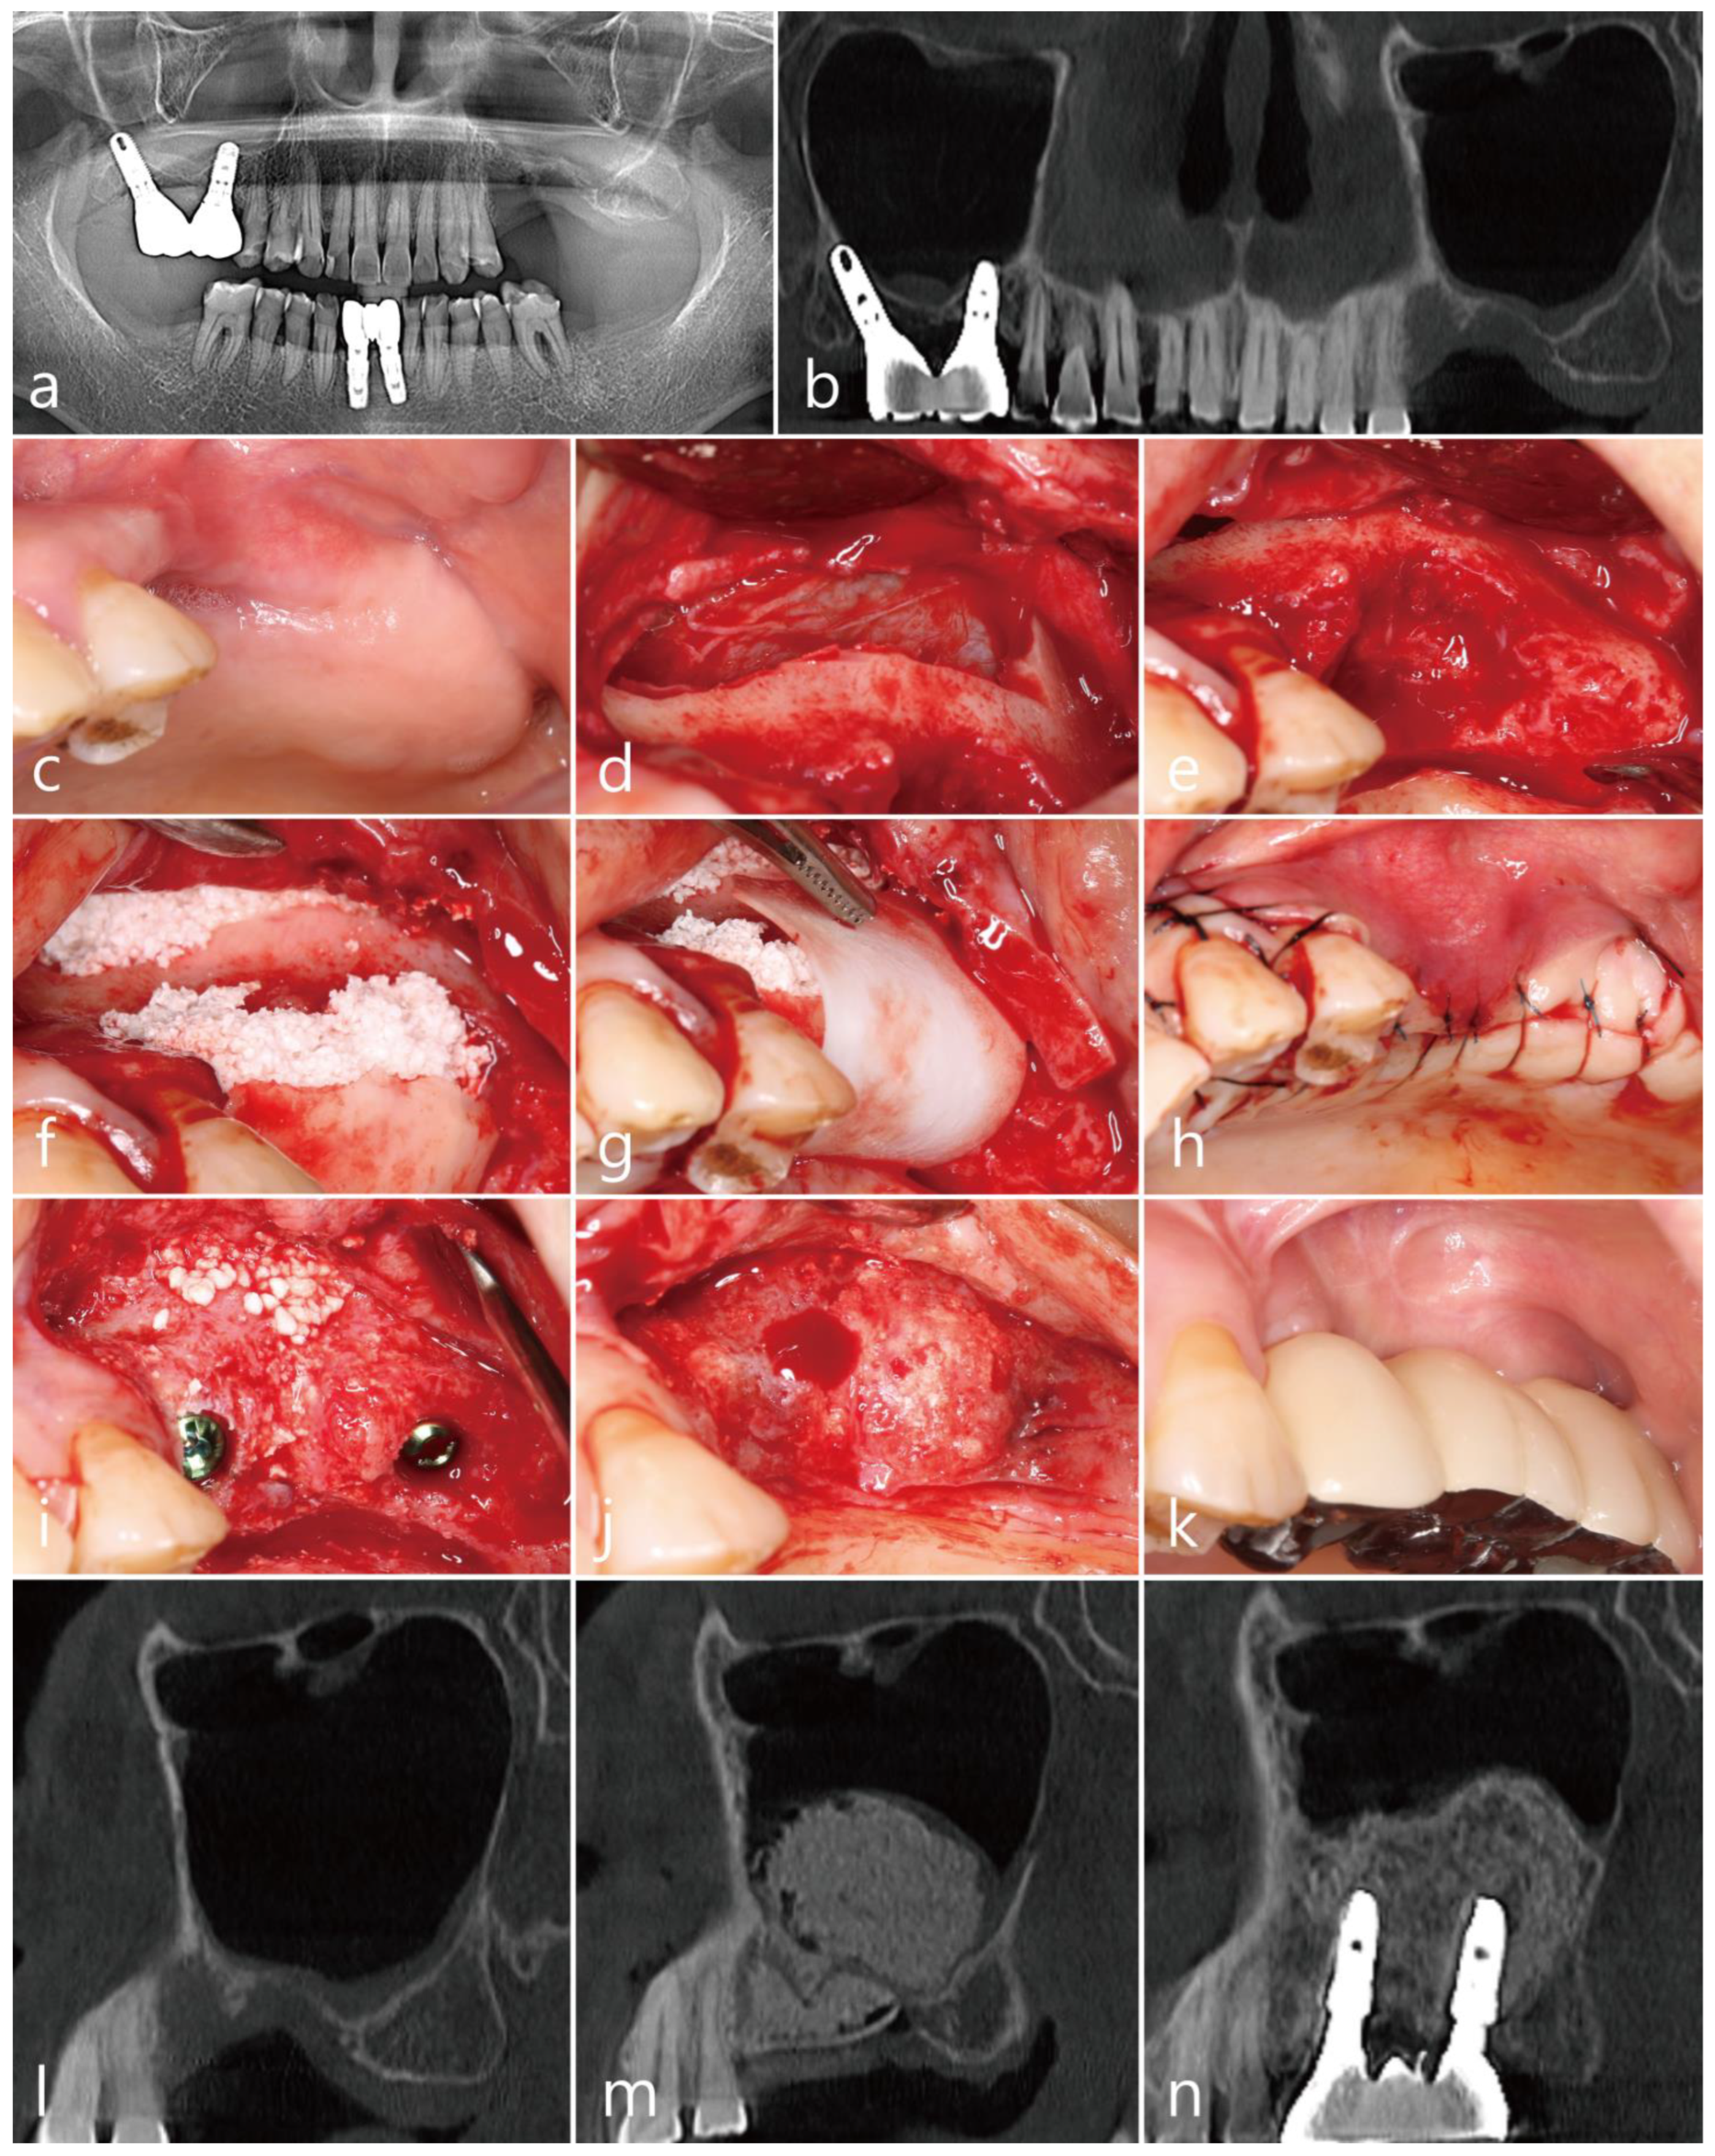

The patient was a 72 year old nonsmoking male (Table 1). An old prosthesis in the maxillary right posterior area was severely mobile, and the patient experienced discomfort during mastication. The patient requested implant-supported restoration after the removal of the old prosthesis. The preoperative panoramic radiograph showed severe bone resorption around teeth #14 and #17. A panoramic image of the CBCT before the surgery showed bony defects around the teeth and severe sinus mucosal thickening (Figure 4a,b).

Tooth extraction, MSA, and implant placement were planned simultaneously. Under local anesthesia with 2% lidocaine (containing 1:100,000 epinephrine), the mucoperiosteal flaps were reflected after extractions of the #14 and #17 teeth in the right maxillary posterior region. The lateral sinus window site was prepared using a #6 round bur (Ø1.6 mm; Azdent, Zhengzhou, Henan Province, China) (Figure 4c). The lateral bony window was obtained (Figure 4d). The sinus membrane was detached and elevated using a sinus elevation instrument (Genoss Co., Ltd., Suwon, Republic of Korea) without perforation. Three implants (Implantium, Dentium Co., Ltd., Suwon, Republic of Korea) were placed after MSA using an Osteon III (particle size 0.5–1.0 mm; Genoss Co., Ltd., Suwon, Republic of Korea) (Table 1). A severe bony defect was observed at the mesial site of the implant placed in the #15 site (Figure 4e). The obtained lateral sinus bony window was cautiously trimmed and placed in the mesial bony defect (Figure 4f). In the residual defect around the grafted lateral sinus bony window, a particulate bone graft substitute (Osteon III; particle size 0.2–0.5 mm; Genoss Co., Ltd., Suwon, Republic of Korea) was grafted (Figure 4g). The wound was covered with a resorbable collagen membrane (Genoss Co., Ltd., Suwon, Republic of Korea) (Figure 4h) and closed with 5-0 nylon. Antibiotics (ciprofloxacin; 500 mg; Ildong Pharmaceutical Co., Ltd., Seoul, Republic of Korea) and a nonsteroidal anti-inflammatory drug (Etodol; 200 mg; Yuhan Co., Ltd., Seoul, Republic of Korea) were prescribed for two weeks. No complications occurred during the healing, and the wound was not exposed (Figure 4i). The uncovering was performed six months after the surgery. The mesial bony defect around implant #15 was completely resolved, and the grafted lateral sinus bony window was well incorporated with the surrounding native bone (Figure 4j). The final prosthesis was delivered two months after the uncovering procedure (Figure 4k).

On the panoramic radiograph after the prosthesis delivery, the mesial bony defect of the #15 implant was filled with the grafted lateral sinus bony window and particulate bone graft (Figure 4l). The panoramic image of the CBCT scan showed a reduced sinus mucosal thickening and the incorporation of the grafted lateral sinus bony window with the surrounding native bone (Figure 4m). The coronal CBCT scans showed PSAAs on both sides. The diameter of the PSAA was 1.1 mm, and the vertical position from the floor of the right maxillary sinus was 19.9 mm (Table 1). On the coronal image of the CBCT at the #15 implant, the mesial bony defect was well resolved (Figure 4n). The coronal CBCT scan at the #16 implant (Figure 4o) showed reduced sinus mucosal thickening compared to the preoperative CBCT scan (Figure 4b).

Figure 4. Case 4: (a) preoperative panoramic radiograph; (b) panoramic image of the preoperative CBCT scan; (c) after flap reflection, the lateral bony window was prepared; (d) obtained lateral bony window; (e) implants were placed after the maxillary sinus augmentation; (f) the lateral bony window was cautiously trimmed and placed on the mesial bony defect; (g) additionally, particulate bone graft was used to fill the gap; (h) a resorbable collagen membrane was placed on the grafted site; (i) a clinical view at six months after surgery; (j) the grafted lateral bony window was well integrated with the surrounding native bone; (k) clinical view after prosthesis delivery; (l) panoramic radiograph at six months after prosthesis delivery; (m) panoramic image of the CBCT at six months after prosthesis delivery; (n) coronal image of the CBCT scan showing posterior superior alveolar arteries on both sides; (o) coronal image of the CBCT scan showing reduced mucosal thickening on the right maxillary sinus.